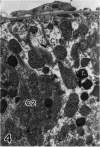

Abundant inflammatory cells such as polymorphonuclear leucocytes and macrophages accumulated and adhered to the endothelial surface of glomerular and intertubular veins and capillaries in rat kidneys after administration of bacterial lipopolysaccharide (LPS). There was also damage to both endothelial cells and proximal tubular cells, including intracytoplasmic oedema, and an increase in the number of lysosomes in the proximal tubular cells in the LPS-treated samples. Immunocytochemistry was used to demonstrate tumour necrosis factor (TNF) and leukotriene (LTR) in both LPS-treated and control samples. Immunoreactive LTR seen in the lysosomes of inflammatory cells attached to the endothelial cell surface may indicate the onset of endothelial cell damage. Positive immunoreactive TNF and LTR were seen on the endothelial cell surface only in the LPS-treated samples, indicating that TNF and LTR may enhance the adhesion of leucocytes to endothelium. Positive reactions of TNF and LTR in lysosomes of the mesangial cells suggest that lysosomes of such cells may be involved in the synthesis and storage of TNF and LTR. In addition to these reaction sites, lysosomes of proximal tubular cells were immunoreactive for LTR. These endogenous LTRs may be implicated in the degeneration of the proximal tubular cells.